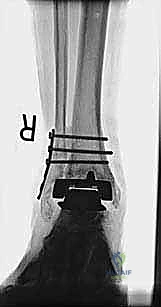

- الأشعة السينية مع تحميل الوزن (Weight-bearing X-rays): لتقييم الزوايا الميكانيكية وتحديد مدى هبوط المفصل أو وجود كسور في الكعب.

* دمج الكاحل (Ankle Arthrodesis): إذا كان التآكل العظمي هائلاً ولا يسمح بتركيب مفصل جديد، يتم إزالة المفصل الصناعي ودمج عظمة الساق مع عظمة الكاحل باستخدام مسامير وصفائح معدنية وطعوم عظمية.

علاج هذه الكسور يتطلب مهارة فائقة من الدكتور محمد هطيف، حيث يتم استخدام تقنيات الجراحة الميكروسكوبية وتثبيت الكسور باستخدام صفائح معدنية دقيقة ومسامير (Locking Plates) دون المساس بثبات المفصل الصناعي، أو يتم دمج علاج الكسر ضمن عملية مراجعة المفصل الكلية إذا كان المفصل نفسه تالفاً.

يتم إدخال المفصل الجديد المخصص للمراجعة، والذي يحتوي غالباً على سيقان (Stems) تدخل عميقاً في عظمة الساق وعظمة الكاحل لضمان الثبات الميكانيكي. في حال وجود كسور في الكعب، يتم تثبيتها في هذه المرحلة.